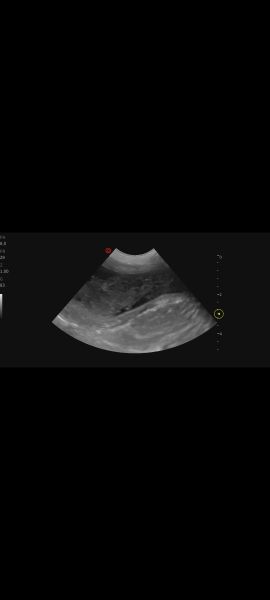

Hi, my vet performed an ultrasound on 7 year old lab mix because of an UTI .She said her bladder walls look thickened and spongy. She's concerned. Can you tell anything? I'll try to add more pics under commentsScreenshot_20251230_161511_PhotosScreenshot_20251230_161500_PhotosScreenshot_20251230_161447_Photos

Screenshot_20251230_161436_PhotosScreenshot_20251230_161425_PhotosScreenshot_20251230_161413_Photos